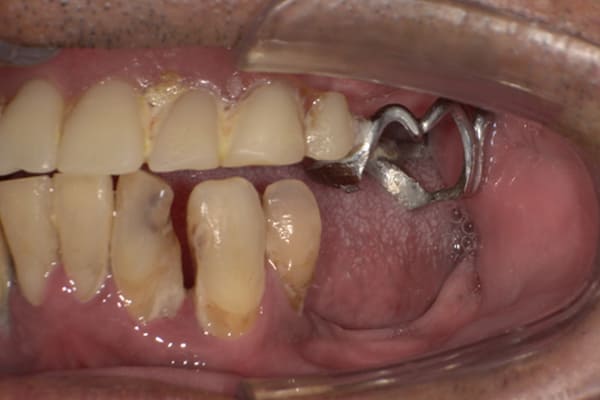

症例レポート[CASE.06]

下歯がぐらぐらで痛い、

咬めるようになりたい

- 性別・年齢

- 男性(70代)

- 主訴

- 下歯がぐらぐらで抜けそうで痛い、何でも咬めるようにしてほしい

- 治療

-

- 上顎精密金属床部分入れ歯

- 下顎精密金属床部分入れ歯

- 陶材焼付鋳造冠 4歯

- 磁性アタッチメント 1歯

- 治療期間

- 約6か月間

- 費用

- 上顎精密金属部分入れ歯:55万円

- 下顎精密金属部分入れ歯:77万円

(治療用義歯含、咬合平面等修正) - 陶材焼付鋳造冠:16.5万円×3歯

(ミリング加工) - 陶材焼付鋳造冠:14.3万円×1歯

(ミリングなし) - 磁性アタッチメント:11万円×1歯

(白金加金)

合計:157.3万円(税込)

奥歯がなくなり放置されていたため、前歯に負担がかかり、歯周病も併発されており歯がぐらぐらでお痛みも伴う状態でした。

可能な限り残せる歯は保存し虫歯治療を行い、どうしても残せないお痛みの歯のみ抜歯を行いました。

陶材焼着付鋳造冠 ミリングラべット加工

残りの歯が少ない場合は、入れ歯が動きやすく、またご自身の歯にも負担がかかるため、残りの歯の被せ物、入れ歯ともに、歯に負担がかかることを最小限にした特殊な加工を行い、歯を長持ちさせる設計としました。